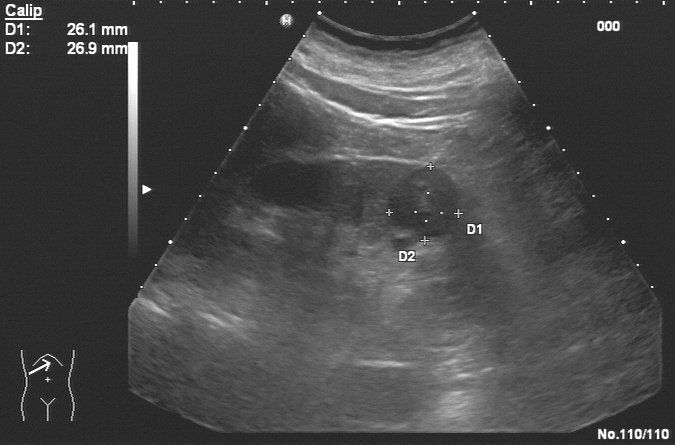

Sonographie des Abdomens

Mit der Ultraschalluntersuchung des Abdomens können die Organe des Bauchraums untersucht werden. Der Schallkopf sendet Ultraschallwellen aus, diese werden je nach Konsistenz des Gewebes absorbiert oder reflektiert. Der Schallkopf empfängt die reflektierten Wellen und wandelt diese in elektrische Impulse um, welche auf dem Bildschirm dargestellt werden. Diese Bilder zeigen Größe, Form und Struktur der untersuchten Organe. Die Beurteilbarkeit ist individuell unterschiedlich und kann durch Übergewicht und Luft im Magen-Darmtrakt beeinträchtigt sein. Besonders geeignet ist die Sonographie zur Feststellung von Erkrankungen der Leber, Nieren, Gallengängen und Bauchspeicheldrüse. Bezüglich Magen und Dickdarm ist die Gastroskopie bzw. Koloskopie überlegen.